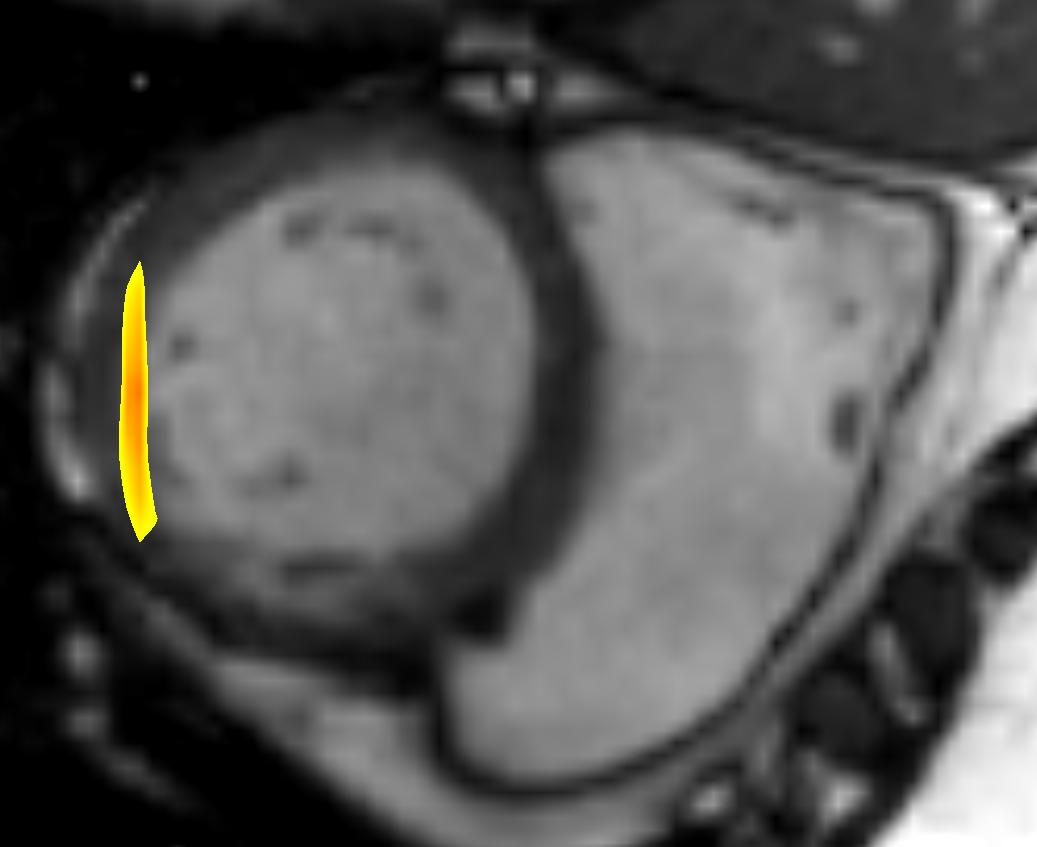

For the cardiac datasets the DVF for mapping the systolic phase to diastolic phase showed better results (DSC: 0.90, HD: 10.35 mm, ASSD: 1.49 mm) compared to the registration from diastolic to systolic phase (DSC: 0.81, HD: 13.12 mm, ASSD: 1.95 mm). We attribute this direction-dependent behaviour to the resampling of the Sunnybrook datasets. In the diastolic images the border of the LV segmentation is in the area of a high gradient in the deformation field where small and large deformations meet. Due to the nearest neighbour interpolation used for resampling the segmentation masks, the mask for interpolated slices is either too small or too large with respect to the linearly interpolated image slices. An example is shown in Fig. 3. However, to exclude an impact of the networks design we repeated the registration with switched input channels. The repeated experiments showed similar results and confirm the more accurate evaluation results from systolic to diastolic phase. Another point that contradicts a methodological failure is that for the lung datasets the better performance was distributed equally.

a) x,y-plane of SC-HYP-38

a) x,y-plane of SC-HYP-38

b) SC-HYP-38 along z-axis

b) SC-HYP-38 along z-axis

e) SC-N-3 with overlayed image foldings

(Jacobi determinant 0)

e) SC-N-3 with overlayed image foldings

(Jacobi determinant 0)